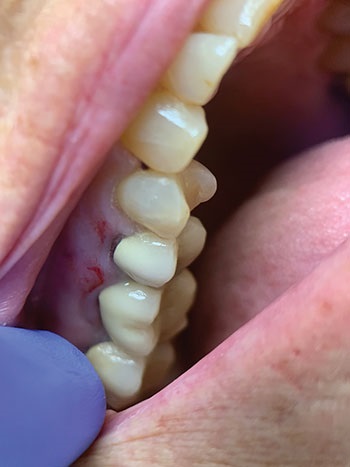

A dental impression of the maxillary left quadrant was made using a temporary quadrant tray with a medium body monophase vinyl poly siloxane dental impression material (Fig. 3). Following the impression, crown preparations were cut on teeth #12 and #14 to prepare them as abutments for the temporary three-unit bridge, leaving tooth #13 intact to await extraction after preparation of the abutment teeth (Fig. 4).

Fig. 4: Teeth #12 and #14 crown preparations. #13 left intact.